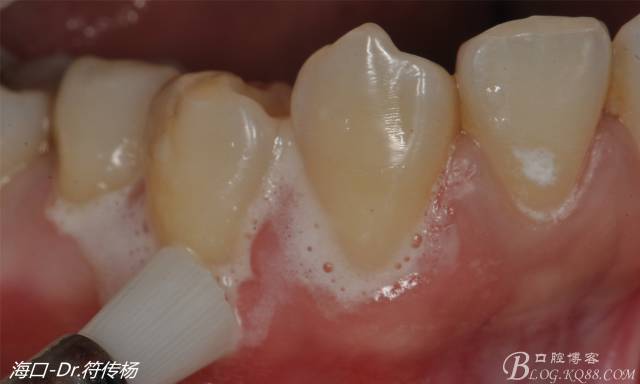

從病例圖片我們可以看到44牙頰側(cè)牙齦出現(xiàn)明顯萎縮

術(shù)前評估:退縮的齦緣在MGJ冠方 近遠中牙槽嵴頂高度正常 屬于Miller -Ι類牙齦退縮 所有術(shù)后可以完全覆蓋

我們首先需要使用拋光刷+拋光膏清潔根面

然后使用EDTA處理根面2min利于牙周附著(有爭議)